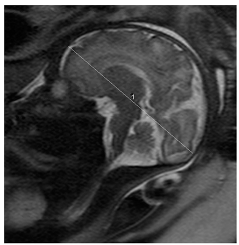

- The pictures below are samples of our manual measurement.

- Fetal brain extraction: To initiate the measurement process, we employ the Dynamic U-Net tool, which is a deep learning pipeline based on the nnU-Net adaptive framework for U-Net-based medical image segmentation. Specifically, we utilize the PyTorch-based MONAIfbs (MONAI fetal brain segmentation) toolkit to perform automatic fetal brain segmentation on HASTE-like MR images.

- Defining the length and width of the brain: After successfully obtaining the brain mask, we utilize OpenCV for further analysis. We first apply the “findContours” function to extract the edges of the fetal head mask from the MRI images. Subsequently, we employ the “convex hull” function to determine the envelope, essentially creating a simplified outline of the fetal head. Then, the “minAreaRect” function identifies the minimum enclosing rectangle around this envelope. This rectangle is essential in measuring the brain dimensions.

- Measuring perimeter, length (FOD), and width (BPD): To calculate the perimeter of the fetal head (HC), we use the “arcLength” function, which provides the path length of the contours. Simultaneously, the “minAreaRect” function not only identifies the rectangle but also gives us the width and height of the fetal head. These dimensions are used to measure the width (BPD) and length (FOD) of the brain.

- Choosing the median of axial series: Typically, patients have multiple sequences, such as axial, sagittal, and coronal. We address this by choosing the median of all axial series as the final automatic measurement result, ensuring a consistent and reliable outcome.